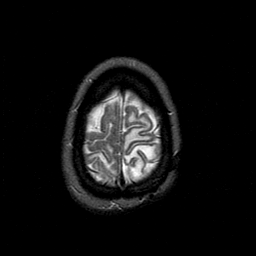

MR Study #1 -- Slice #46

[Home][Help][Clinical][Tour 1][Tour 2][Tour 3] Slice 46